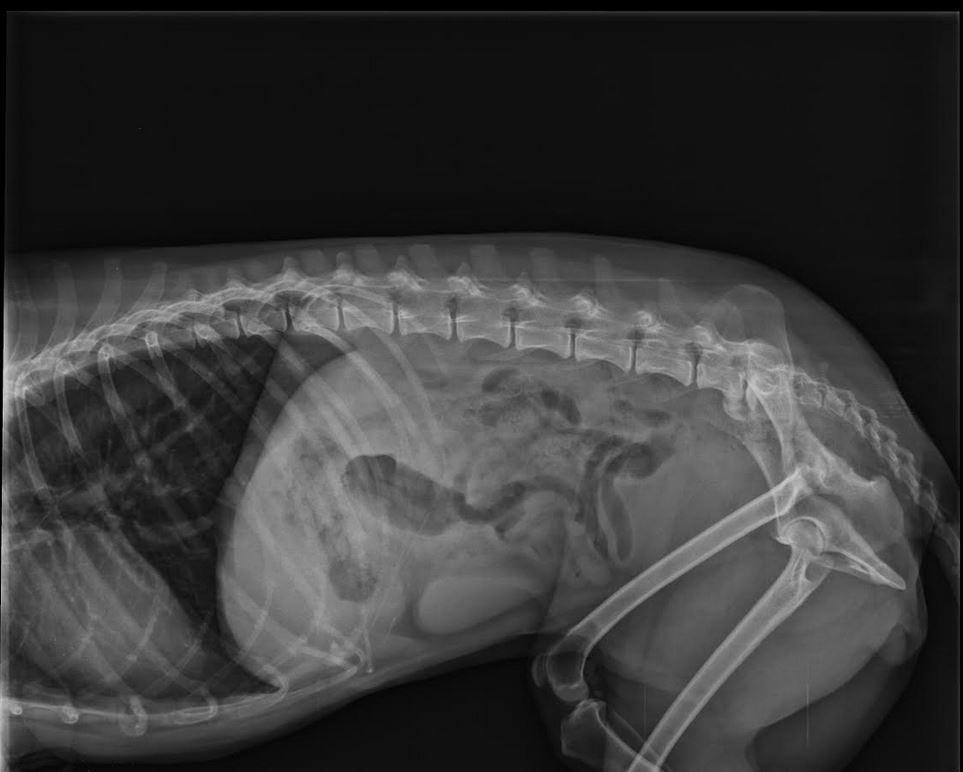

Everything posted by Sara2011

12. O matko, jakie niedobre wiadomości. A tak się cieszyłam, że tych ataków więcej nie było. A jednak są :(. U mnie Frezja też połykała karmę, nie gryzła jej.